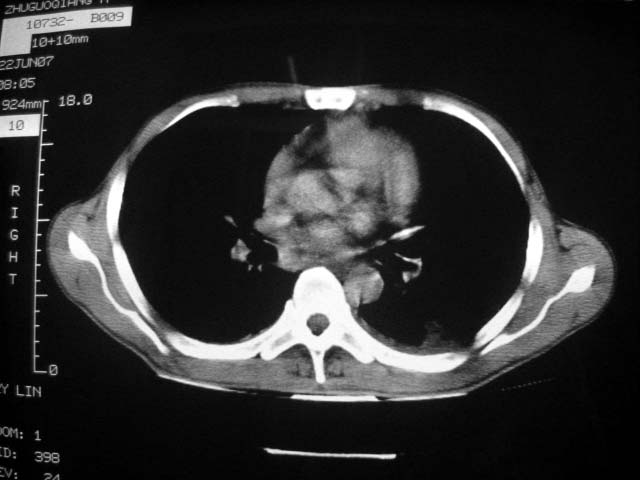

标题: CT7988D:近期图像 出乎意料!

从ct7988c 至今未用任何抗生素及抗痨药,维持保肝治疗。患者低热、咳血渐消失。

07年6月22号复查

前几次大家认为是转移癌,但此次复查病灶却明显吸收好转,不支持诊断。请大家讨论。[emb10]

双侧继发性肺结核伴两肺播散灶.双侧胸腔少量积液

近2个月病灶变化较大,应是感染性病变,首先考虑金黄色葡萄球菌感染。

根据前后片比较应该考虑迁徙性肺脓肿,回帖相差甚远是因为前后片变化太大出乎大家意料之外,这就是影象诊断要结合临床复查对比的必要性,

回顾既往片,病变明显吸收,缩小,未经治疗,不支持肺转移瘤,可能为肺结节病或韦格氏肉芽肿